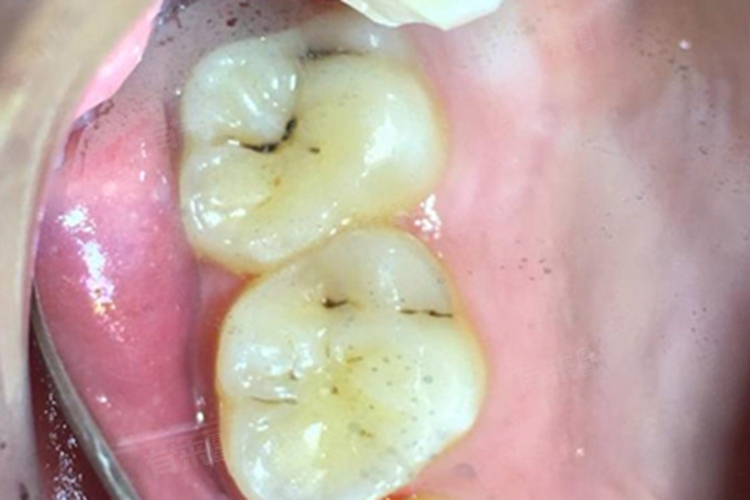

牙齿表面出现黑线是常见的口腔问题,可能由色素沉积、龋齿、牙釉质发育不全等多种原因引起。其处理方法需根据具体病因决定,包括专业洁牙、补牙、树脂修复等。

2、龋齿:龋齿也是造成牙齿上出现黑线的一个重要原因。当口腔细菌产生酸性物质侵蚀牙齿时,会在牙齿表面或牙缝间形成黑色的龋洞。早期发现可以通过补牙材料填补来修复;如果龋坏深入牙髓,则需要进行根管治疗,并可能需要安装牙冠保护受损牙齿。

3、牙釉质发育不全:牙釉质发育不全可能导致牙齿表面出现条纹状的黑线。这种情况通常与遗传因素有关,也可能受到孕期营养不良等因素影响。治疗方法取决于病变程度,轻微情况下可通过氟化物治疗增强牙釉质硬度,严重时则需采用贴面或冠修复。